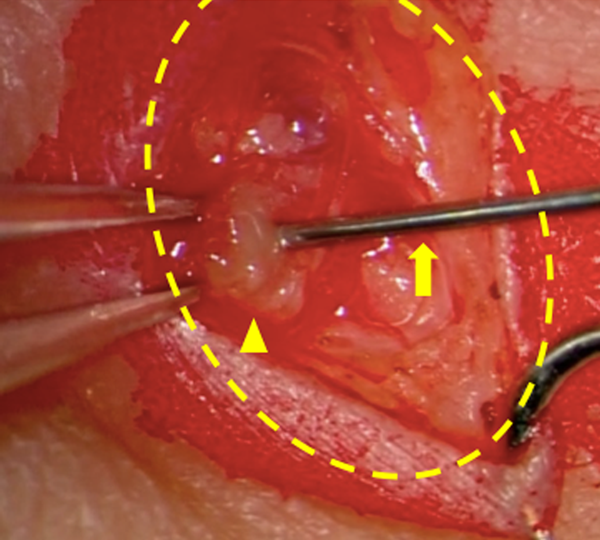

Pediatric Cardiology and Cardiac Surgery 34(3): 135-142 (2018)

Fig. 3 Open direct lymphangiography (Intra operative finding) (Case #2)

Lymph node puncture under microscopic dissection, 30 days old, 800 g. Arrow head: Lymph node, Arrow: 27 G needle, Interrupted circle: skin dissected area.